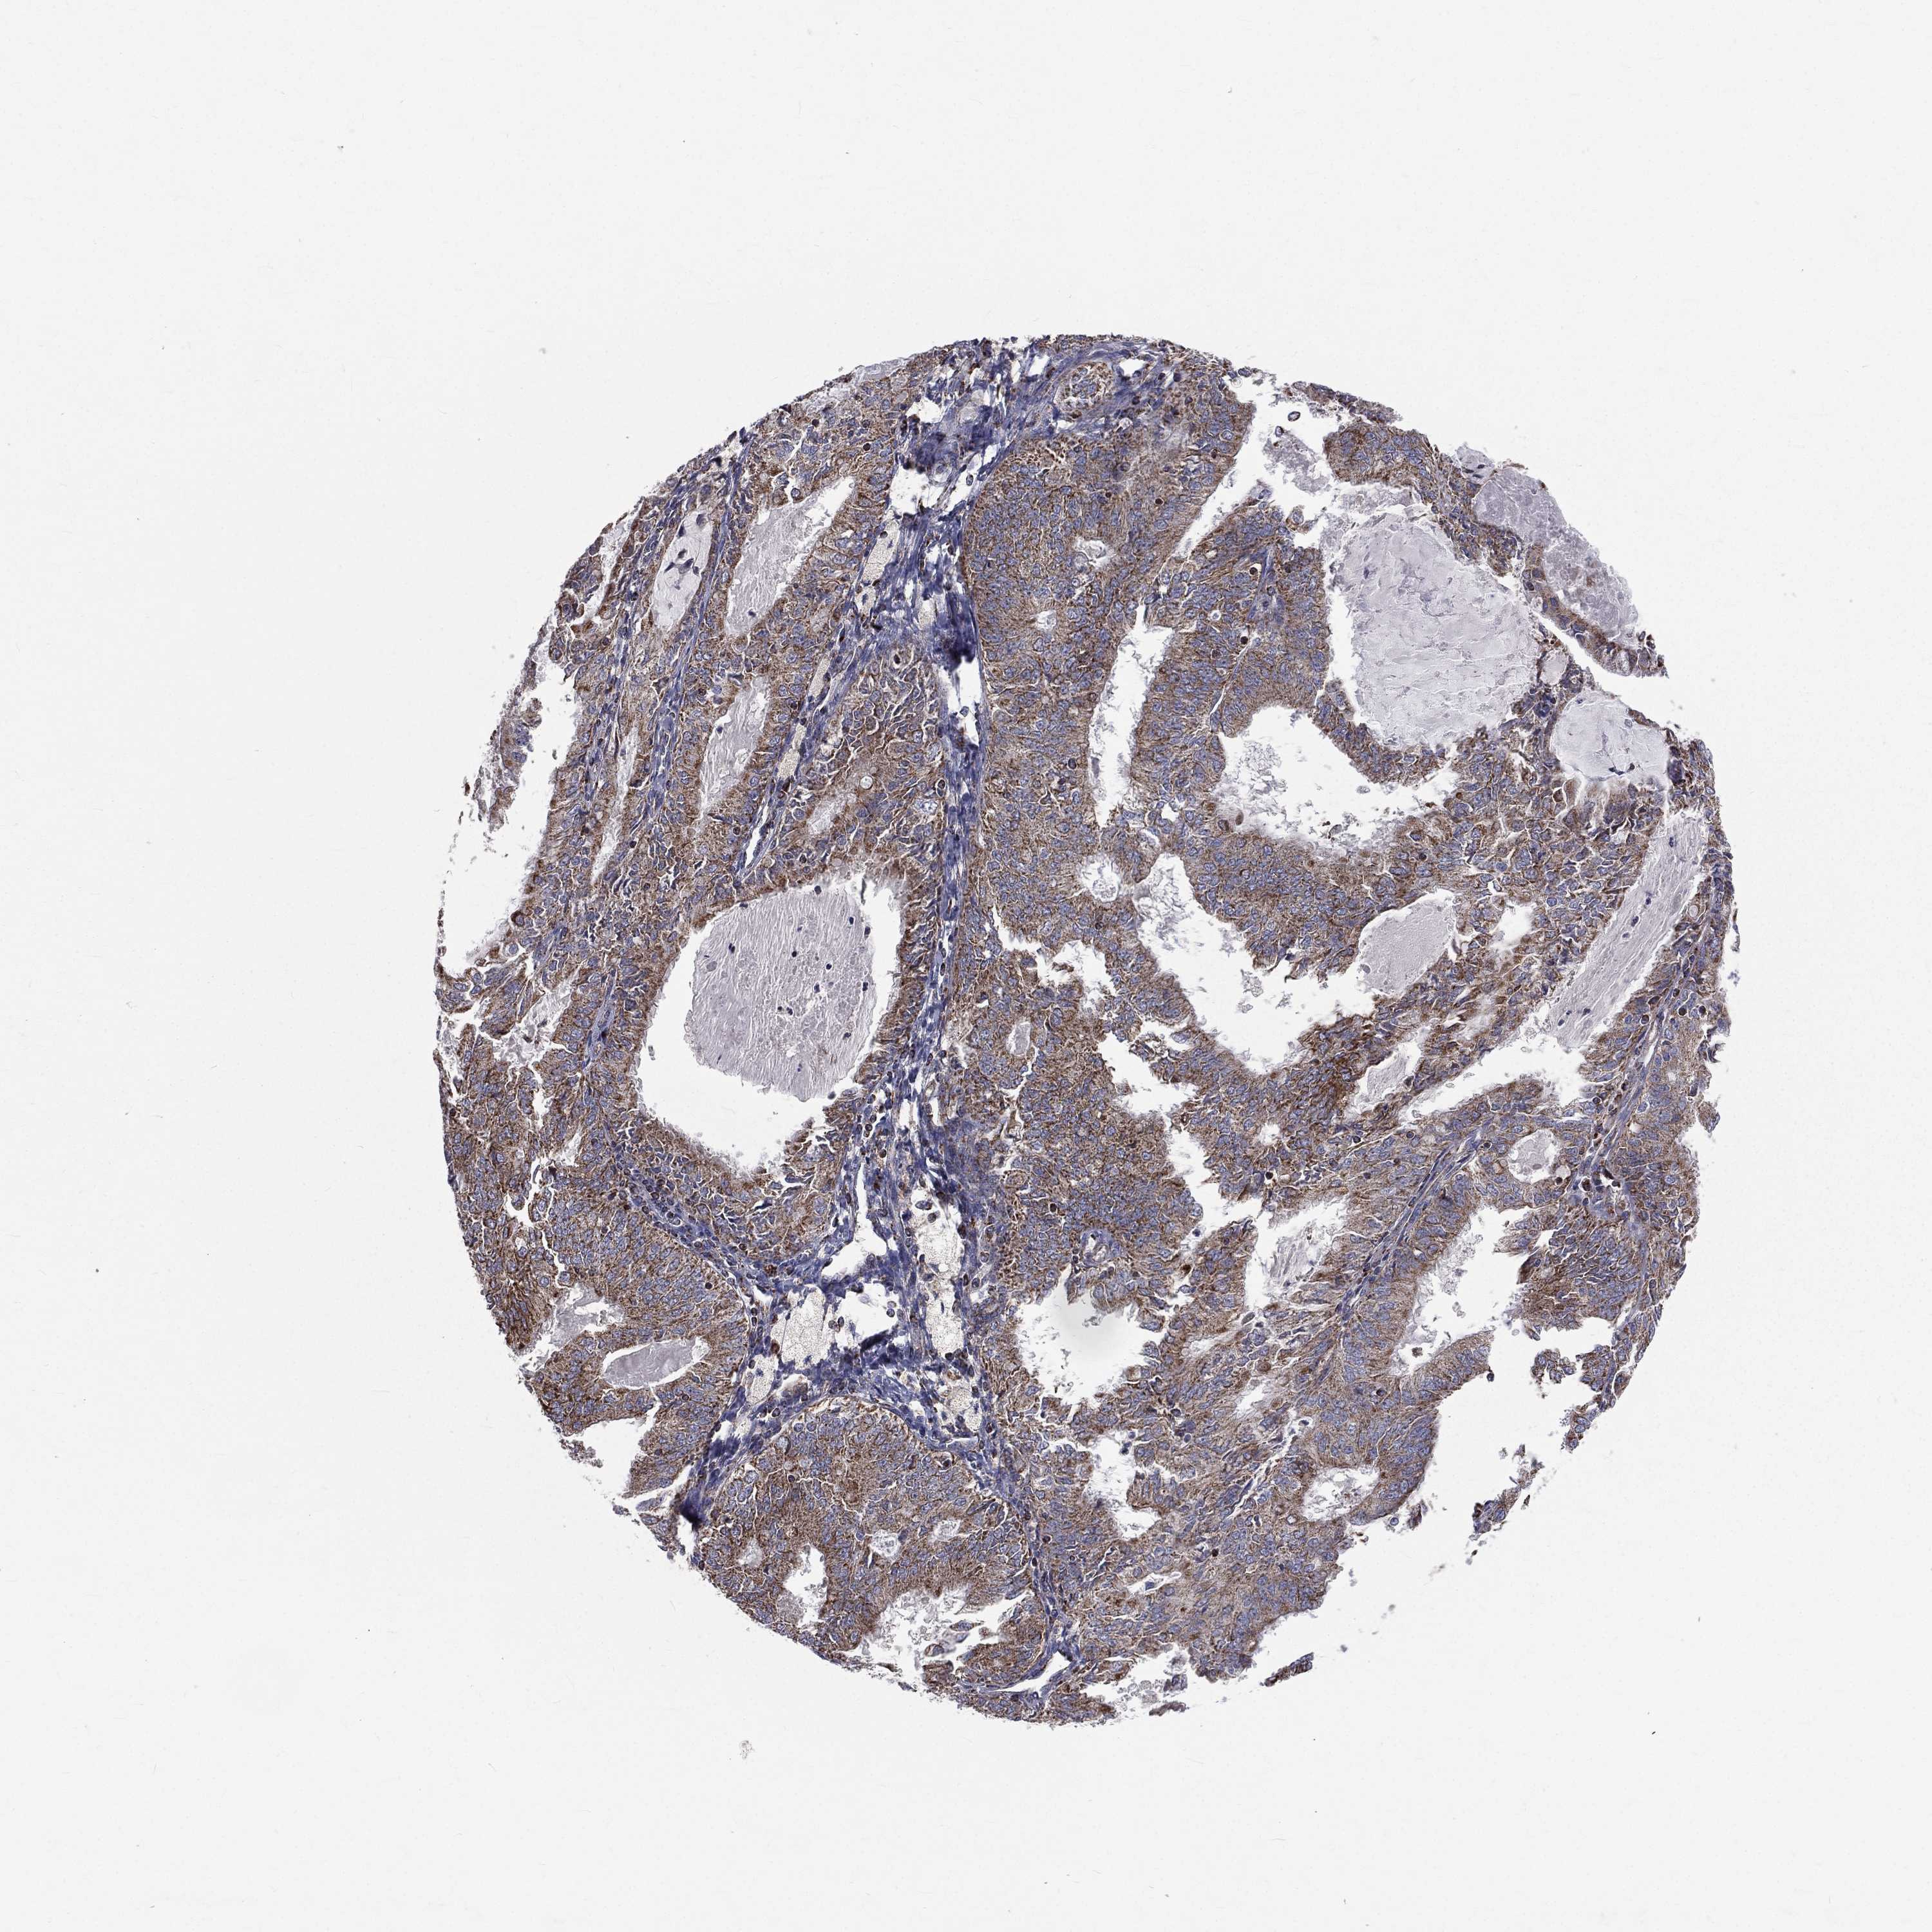

ENDOMETRIAL CANCER - Protein expressioni

A mouse-over function shows sample information and annotation data. Click on an image to view it in a full screen mode. Samples can be filtered based on level of antibody staining by selecting one or several of the following categories: high, medium, low and not detected. The assay and annotation is described here.

Note that samples used for immunohistochemistry by the Human Protein Atlas do not correspond to samples in the TCGA dataset.

Antibody stainingi

Antibody staining in the annotated cell types in the current human tissue is reported as not detected, low, medium, or high, based on conventional immunohistochemistry profiling in selected tissues. This score is based on the combination of the staining intensity and fraction of stained cells.

Each image is clickable and will lead to virtual microscopy that enables deeper exploration of all samples and also displays staining intensity scores, fraction scores and subcellular localization as well as patient and tissue information for each sample.

Antibody HPA044620

Antibody HPA058621

Staining

High

Medium

Low

Not detected

Intensity

Strong

Moderate

Weak

Negative

Quantity

>75%

75%-25%

<25%

None

Location

Nuclear

Cytoplasmic/membranous

Cytoplasmic/membranous,nuclear

Adenocarcinoma, NOS